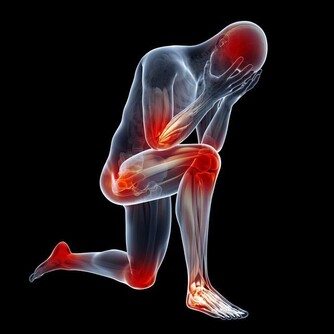

所謂陽虛,是指機體陽氣不足,即俗稱“火力不足”,是氣虛的進一步發展,機能減退或衰退,反應能力低下,代謝熱量不足的一種體能狀態。陽氣不足,一般以脾腎陽氣虛為主,臨床表現為平素怕寒喜暖,手足不溫,口淡不渴,喜熱飲食,飲食生冷則易腹痛腹瀉,或胃脘冷痛,腰膝冷痛,小便清長,大便溏薄,舌體胖嫩,舌苔白滑,脈象沉溺等。

人散步的時候會有很多生理反應,其中一個反應就是滿口生津。這代表你的腎氣、腎精得到補充了,因為在五行學說裡面唾液歸屬於腎水。所以腎陰虛的人口裡會經常乾,缺少唾液,這就是腎精不足了。那麼腎精氣不足會出現哪些症狀呢?常見的有腰膝酸軟、手腳冷、體虛乏力、耳鳴、脫髮、牙齒鬆動、骨質疏鬆、夜尿多、前列腺肥大、性功能減退、不孕不育、腎虧、更年期綜合症。